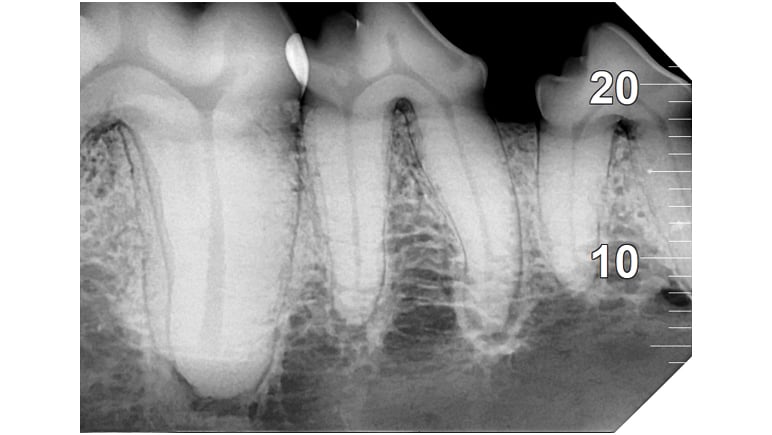

Analyse auf hohem Niveau

Das mit der zugehörigen Software integrierte System bietet hochmoderne Analysewerkzeuge und eine Auswahl spezifischer Filter, um die Lesbarkeit der Bilder gemäß den klinischen Anforderungen zu verbessern: